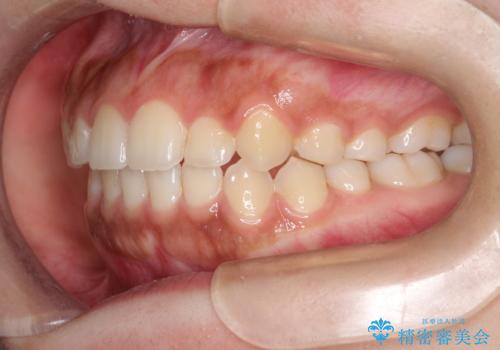

インビザライン 前歯のがたつきを目立たず矯正

- 前歯のがたつきが気になるとのことで来院されました。

インビザラインにて治療を行いました。

わずかに歯と歯の間に隙間を作り、歯列矯正を行いました。

マウスピースをしっかりと使用していただけたので、スムーズに治療を終了することができました。